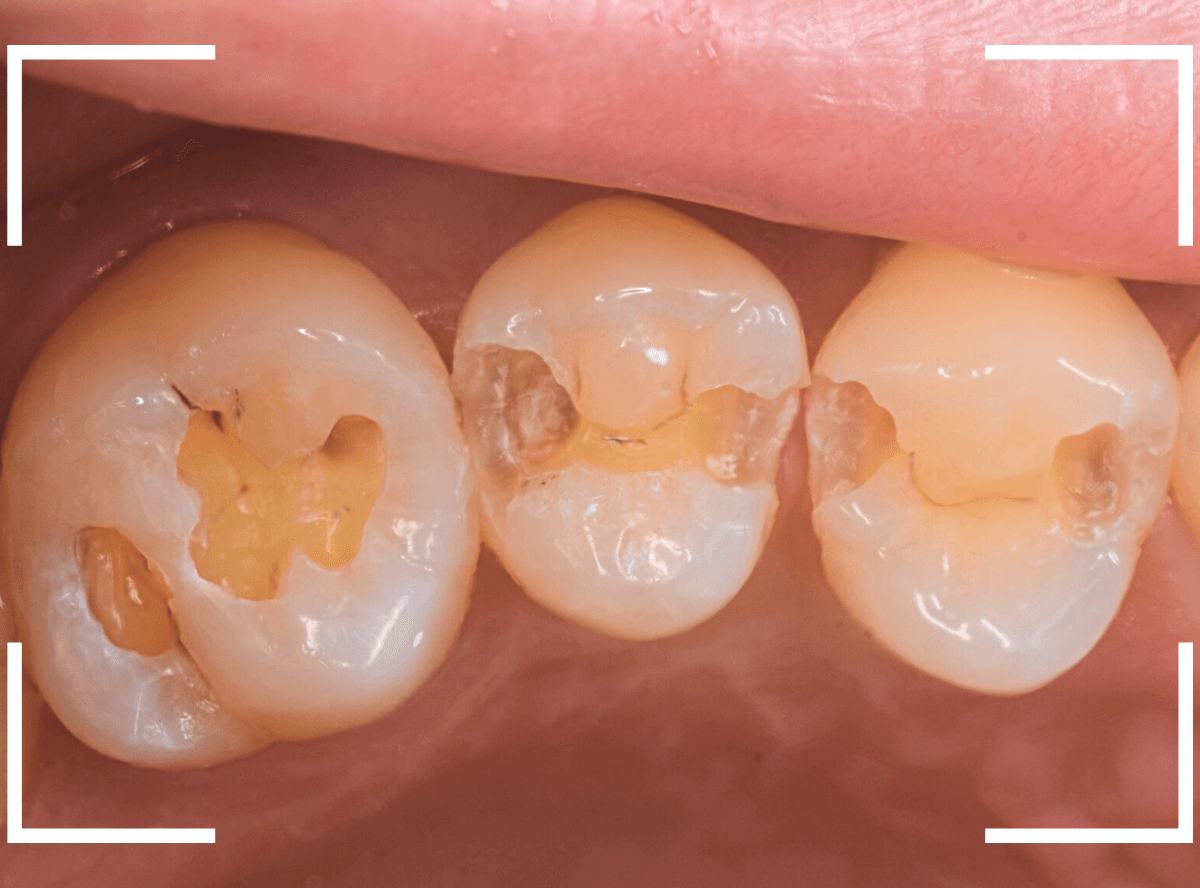

Case.10 レントゲンに写らない側面の虫歯を、少しずつ削って調べる

こちらも、虫歯が歯のあちこちで進行してしまっている患者さんのケースです。

特に側面の虫歯が深そうです。

側面にできた虫歯はレントゲン写真では診断しづらくやっかいです。

今回は「見るからに深そう」ですが。

さすがにレントゲン写真でも虫歯がありそうな事は確認できますが、実際にどうなってるのかはあまりはっきりわかりません。

少しずつ虫歯を除去していきます。

歯の側面から、手前の歯までつながった虫歯になっていました。

手前の歯までの虫歯を除去しました。

歯の後ろ側の側面も、大きな虫歯になっていますので、処置します。

隣の歯との間(隣接面)は、中で虫歯が広く進んでることが多いです。

結局、前後の歯に渡る広い虫歯でした。

レントゲン写真だけでは、ここまでの虫歯は判断できませんでした。